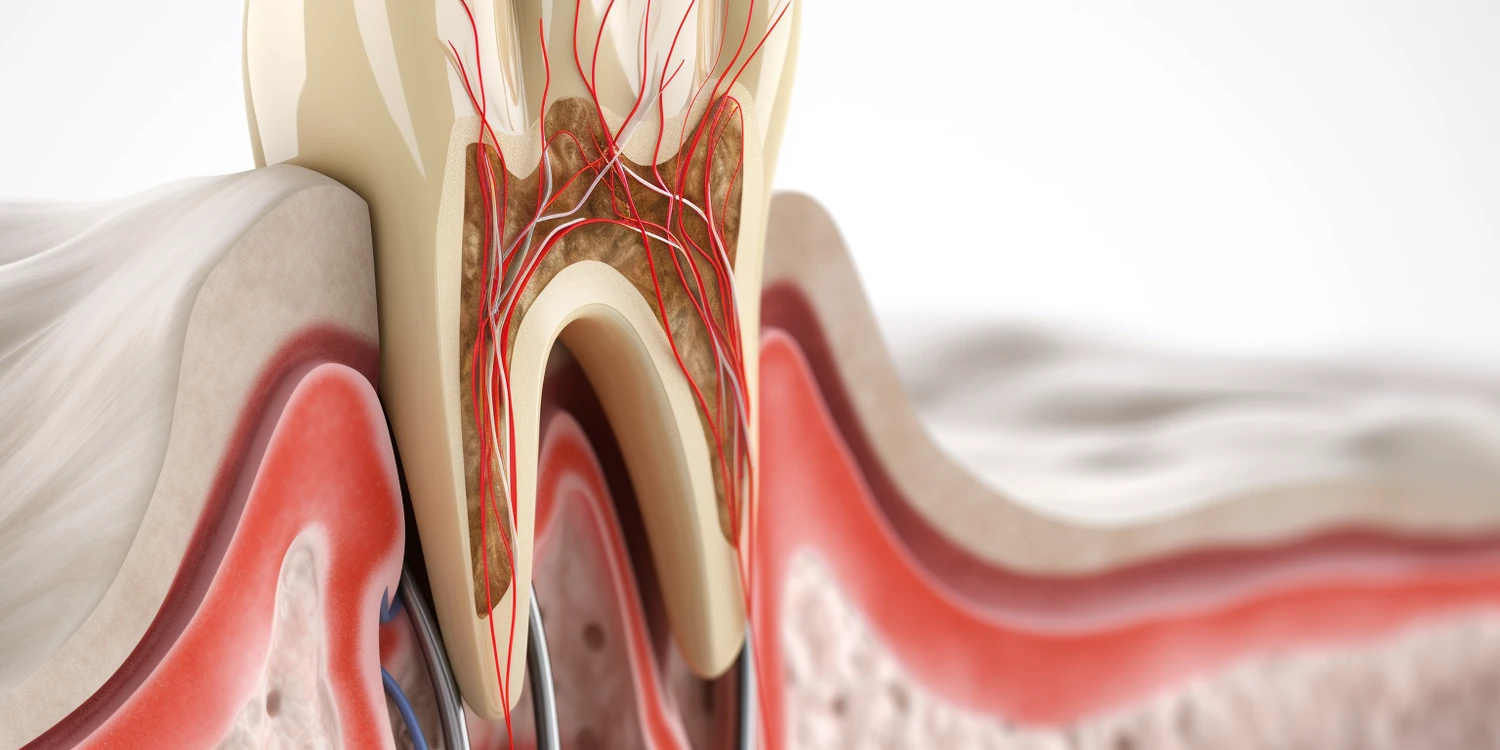

Leczenie kanałowe pod mikroskopem Szczecin

Kiedy tradycyjne metody leczenia kanałowego okazują się niewystarczające, a problem dotyczy głęboko ukrytych lub skomplikowanych zmian w obrębie miazgi zęba, na ratunek przychodzi nowoczesna technologia. Leczenie kanałowe pod mikroskopem w Szczecinie to zabieg, który znacząco podnosi precyzję i skuteczność terapii endodontycznej. Pozwala on stomatologom na pracę z niespotykaną dotąd dokładnością, co przekłada się na lepsze […]

Co to jest dłutowanie zęba?

Dłutowanie zęba to procedura stomatologiczna, która ma na celu usunięcie chorej tkanki zęba, najczęściej w przypadku zaawansowanej próchnicy. W trakcie tego zabiegu dentysta używa specjalnych narzędzi, aby precyzyjnie usunąć zainfekowane lub zniszczone części zęba. Dłutowanie zęba jest często konieczne, gdy inne metody leczenia, takie jak wypełnienia, nie są wystarczające do przywrócenia zdrowia zęba. Proces ten […]

Ile trwa leczenie kanałowe jednego zęba?

Leczenie kanałowe, znane również jako endodoncja, to proces, który ma na celu uratowanie zęba, którego miazga uległa zapaleniu lub zakażeniu. Czas trwania takiego leczenia może się różnić w zależności od wielu czynników. Zazwyczaj jedno leczenie kanałowe jednego zęba trwa od jednej do trzech wizyt u dentysty. Pierwsza wizyta zazwyczaj obejmuje diagnostykę, wykonanie zdjęcia rentgenowskiego oraz […]

Leczenie stomatologiczne przy pomocy mikroskopu?

Leczenie stomatologiczne przy pomocy mikroskopu to nowoczesna metoda, która zyskuje coraz większą popularność wśród dentystów oraz pacjentów. Mikroskopy stomatologiczne umożliwiają lekarzom precyzyjne wykonywanie zabiegów, co znacząco zwiększa ich skuteczność. Dzięki powiększeniu obrazu, dentyści mogą dokładniej diagnozować problemy oraz przeprowadzać skomplikowane procedury, takie jak leczenie kanałowe czy usuwanie próchnicy. W tradycyjnej stomatologii lekarze często musieli polegać […]